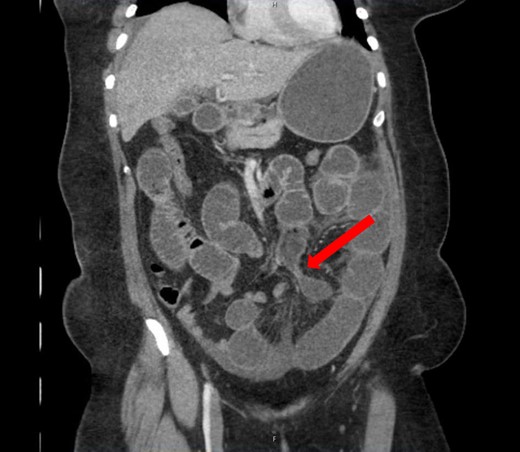

A 40-year-old woman presented to the emergency department with abdominal pain for 4 days. She had previously been seen at an outside hospital 3 days earlier, and was diagnosed with biliary colic. Her pain was constant, and was associated with nausea and vomiting. She had a history of a cesarean section, but no other abdominal surgeries. Her vitals were within normal limits: afebrile at 36.9°C, heart rate 71 beats/minute, blood pressure 143/62 mmHg, respiratory rate 18 breaths/minute, and oxygen saturation 97% on room air. On abdominal exam, she was distended, tender, demonstrated voluntary guarding and was positive for peritonitis. Laboratory values were significant for a white blood cell count of 16.1 K/ul, with 80.2% neutrophils, hemoglobin 14.9 g/dl, hematocrit 45.4%, platelets 349 K/ul and lactic acid 0.9 mEq/L; her chemistry was unremarkable. A computed-tomography (CT) scan of the abdomen and pelvis that was obtained prior to surgical consultation demonstrated the proximal two-thirds of small bowel dilated up to 4 cm, with a sharp transition point in the left mid-abdomen, and collapsed small bowel loops near the cecum. The colon was mostly collapsed. A few distended loops bulged into a paraumbilical hernia, which was 6 cm wide and not the cause of obstruction (Figs 1–3).

Coronal view: arrow pointing to the dumb-bell transition point, where the proximal end of the closed loop small bowel herniated through a hole in the sigmoid epiploica.